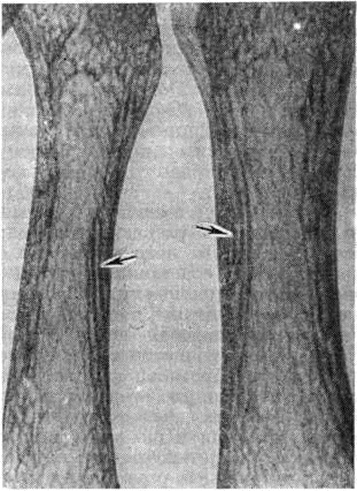

Рис. 2.

Рентгенограмма плюсневых костей стопы при хронической почечной недостаточности: стрелками указано разволокнение кортикального слоя кости (увеличено).